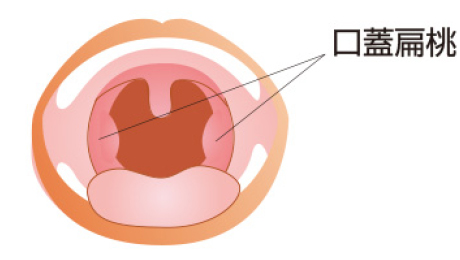

口蓋扁桃肥大、アデノイド肥大」 のどの病気 - 愛知県瀬戸市の耳鼻咽喉科・アレルギー科・気管食道科 こだま耳鼻科クリニック。